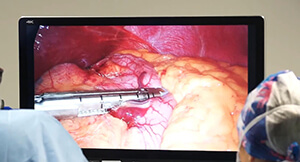

Get a sleeve in Tunisia (Endo Sleeve)

Decision to have a sleeve in Tunisia

The decision to undergo a Sleeve Tunisia operation is primarily motivated by the desire to lose weight, while also responding to health problems related to obesity and associated pathologies.